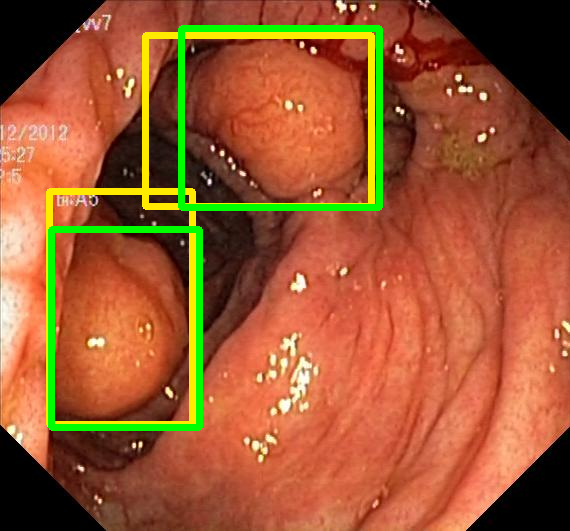

We evaluate the resulting object detection models using the test data, which is pre-processed in the same manner as the validation data, with AP@[.5:.95] (AP for conciseness), AP@.5 (AP5050{}_{50}start_FLOATSUBSCRIPT 50 end_FLOATSUBSCRIPT), and AP@.75 (AP7575{}_{75}start_FLOATSUBSCRIPT 75 end_FLOATSUBSCRIPT) computed for predicted bounded boxes with a confidence score \geq0.05. For all metrics, a higher value indicates better performance. The results are presented in Table VI, and some examples for predicted bounding boxes with a confidence score \geq0.5 are shown in Fig. 1.

RN-HK-MC RN-HK-BT RN-IN-MC RN-IN-BT RN-IN-SL RN-NA-NA Refer to caption Refer to caption Refer to caption Refer to caption Refer to caption Refer to caption Refer to caption Refer to caption Refer to caption Refer to caption Refer to caption Refer to caption VT-HK-MC VT-HK-MA VT-IN-MC VT-IN-MA VT-IN-SL VT-NA-NA Refer to caption Refer to caption Refer to caption Refer to caption Refer to caption Refer to caption Refer to caption Refer to caption Refer to caption Refer to caption Refer to caption Refer to caption

Figure 1: Targets (yellow bounding boxes) and predictions (green bounding boxes) for two randomly selected instances of the Kvasir-SEG test set. For conciseness, we denote ResNet50s with RN, ViT-Bs with VT, Hyperkvasir-unlabelled with HK, ImageNet-1k with IN, MoCo v3 with MC, Barlow Twins with BT, MAE with MA, supervised pretraining with SL, and no pretraining with NA-NA.